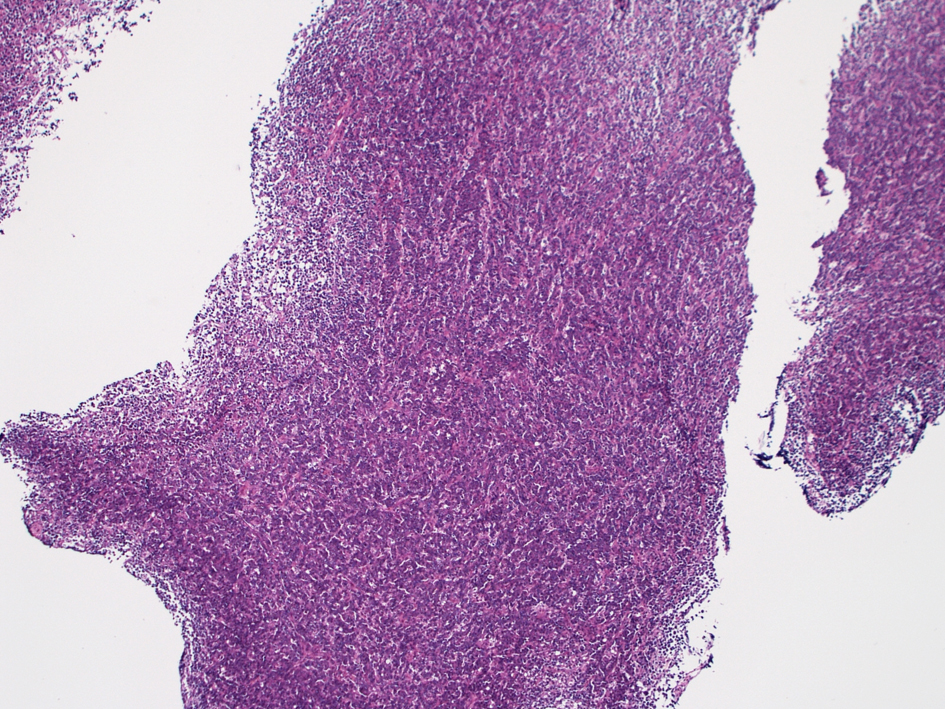

骨髄病変

山梨大学医学部 Dr.大石直輝: 骨髄HEではvesicularな核をもつ大型異型細胞がorganoid pattern, 類上皮様配列をとり増殖している。癌腫の転移と紛らわしい所見。

腫瘍細胞は接着性がみられ, 索状に増殖, 上皮性腫瘍のように見える。